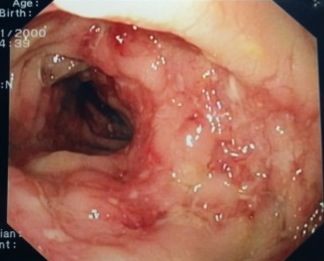

Una bambina di origine indiana, nata in Italia, viene ricoverata per un quadro di distrofia in storia di scarso accrescimento ponderale (Figura 1). All’atto del ricovero: 8 anni, peso 12,5 kg (< 3° percentile), altezza 118 cm (50° percentile), BMI: 9. Non ha storia di infezioni croniche, di alterazioni dell’alvo, di sintomatologia dolorosa né di situazioni di disagio. È stata due volte in India per 30 giorni, 18 e 6 mesi prima del ricovero. Agli esami di primo livello: anemia microcitica con ferritina 300 ng/ml, PCR 14 mg/dl, VES 101 mm/h, calprotectina fecale > 3000 mg/kg, test del sangue occulto nelle feci (SOF) positivo su 3 campioni, esame coproparassitologico negativo, ASCA IgA debolmente positivi, IgG negativi. Mantoux negativa a 72 ore.

Nel frattempo l’esame endoscopico mostra, a livello di colon e ileo terminale, una mucosa con multiple ulcere, tratti edematosi e iperemici, valvola ileocecale beante, deformata, ulcerata (Figura 3); quadro compatibile con morbo di Crohn. Campioni bioptici vengono inviati in Anatomia patologica e in Microbiologia: flogosi granulomatosa focalmente necrotizzante, colorazione di Ziehl-Neelsen positiva per M. tuberculosis; coltura positiva per M. tuberculosis su biopsia del colon.